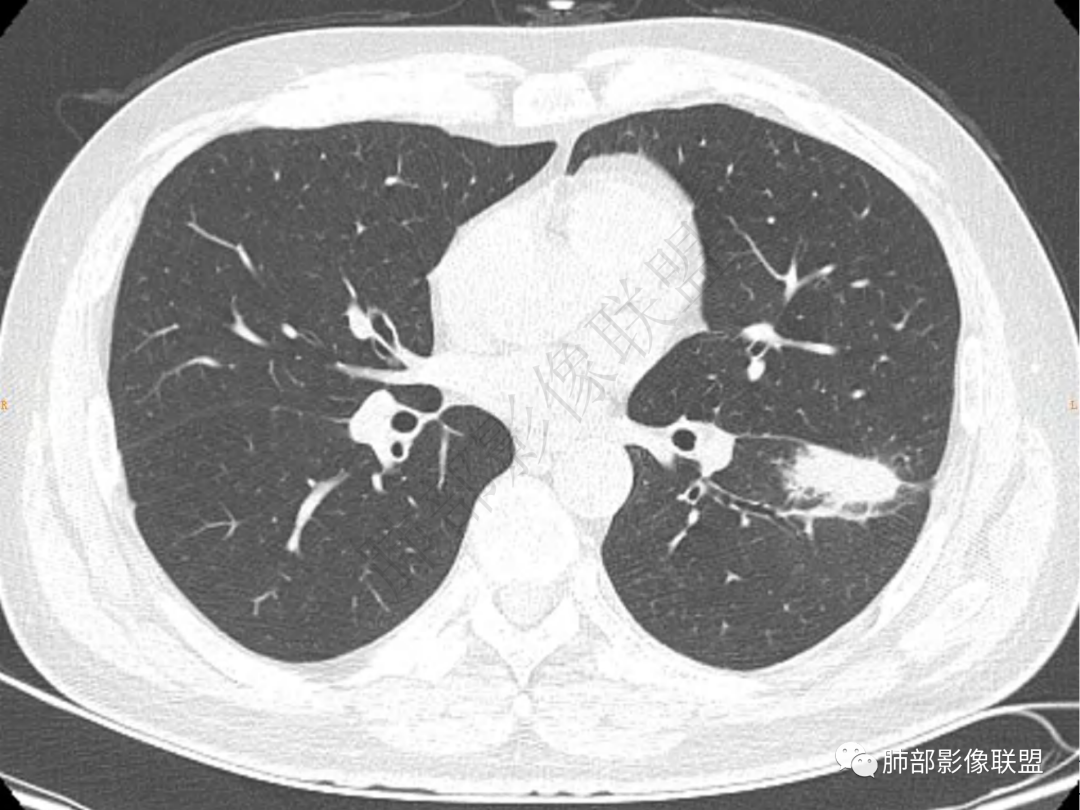

2.左肺下叶团片影,跨背段及内前基底段,实性部分类椭圆形,密度不甚均匀,可见毛刺及棘状突起,未见典型分叶及胸膜凹陷。病灶上下缘可见相应肺段支气管旁进侧出,管壁轻度增厚,未见狭窄阻塞。

3.周边较大范围磨玻璃影,边界相当模糊,小叶增厚明显。注意叶裂另一侧、左肺舌段亦可见磨玻璃影及增厚的小叶间隔。未见明确卫星病灶。

4.实性部分不均匀环形强化并显示一小范围低密度坏死区或空洞。较之肺窗,整体纵隔窗范围较小,提示病灶并不十分密实。抑或为不同时段图像。

5.双肺门及纵隔未见增大淋巴结。未见胸腔积液。